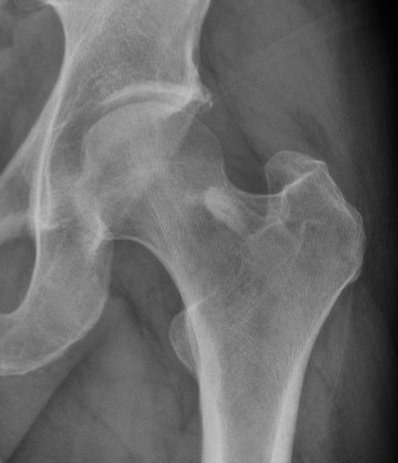

X-ray

Sharply-circumscribed cortical densities

- round or oval in shape with smooth, regular borders

- narrow zone of transition from lesion to cancellous bone

- no evident reaction to the process

Usually < 1 cm in diameter